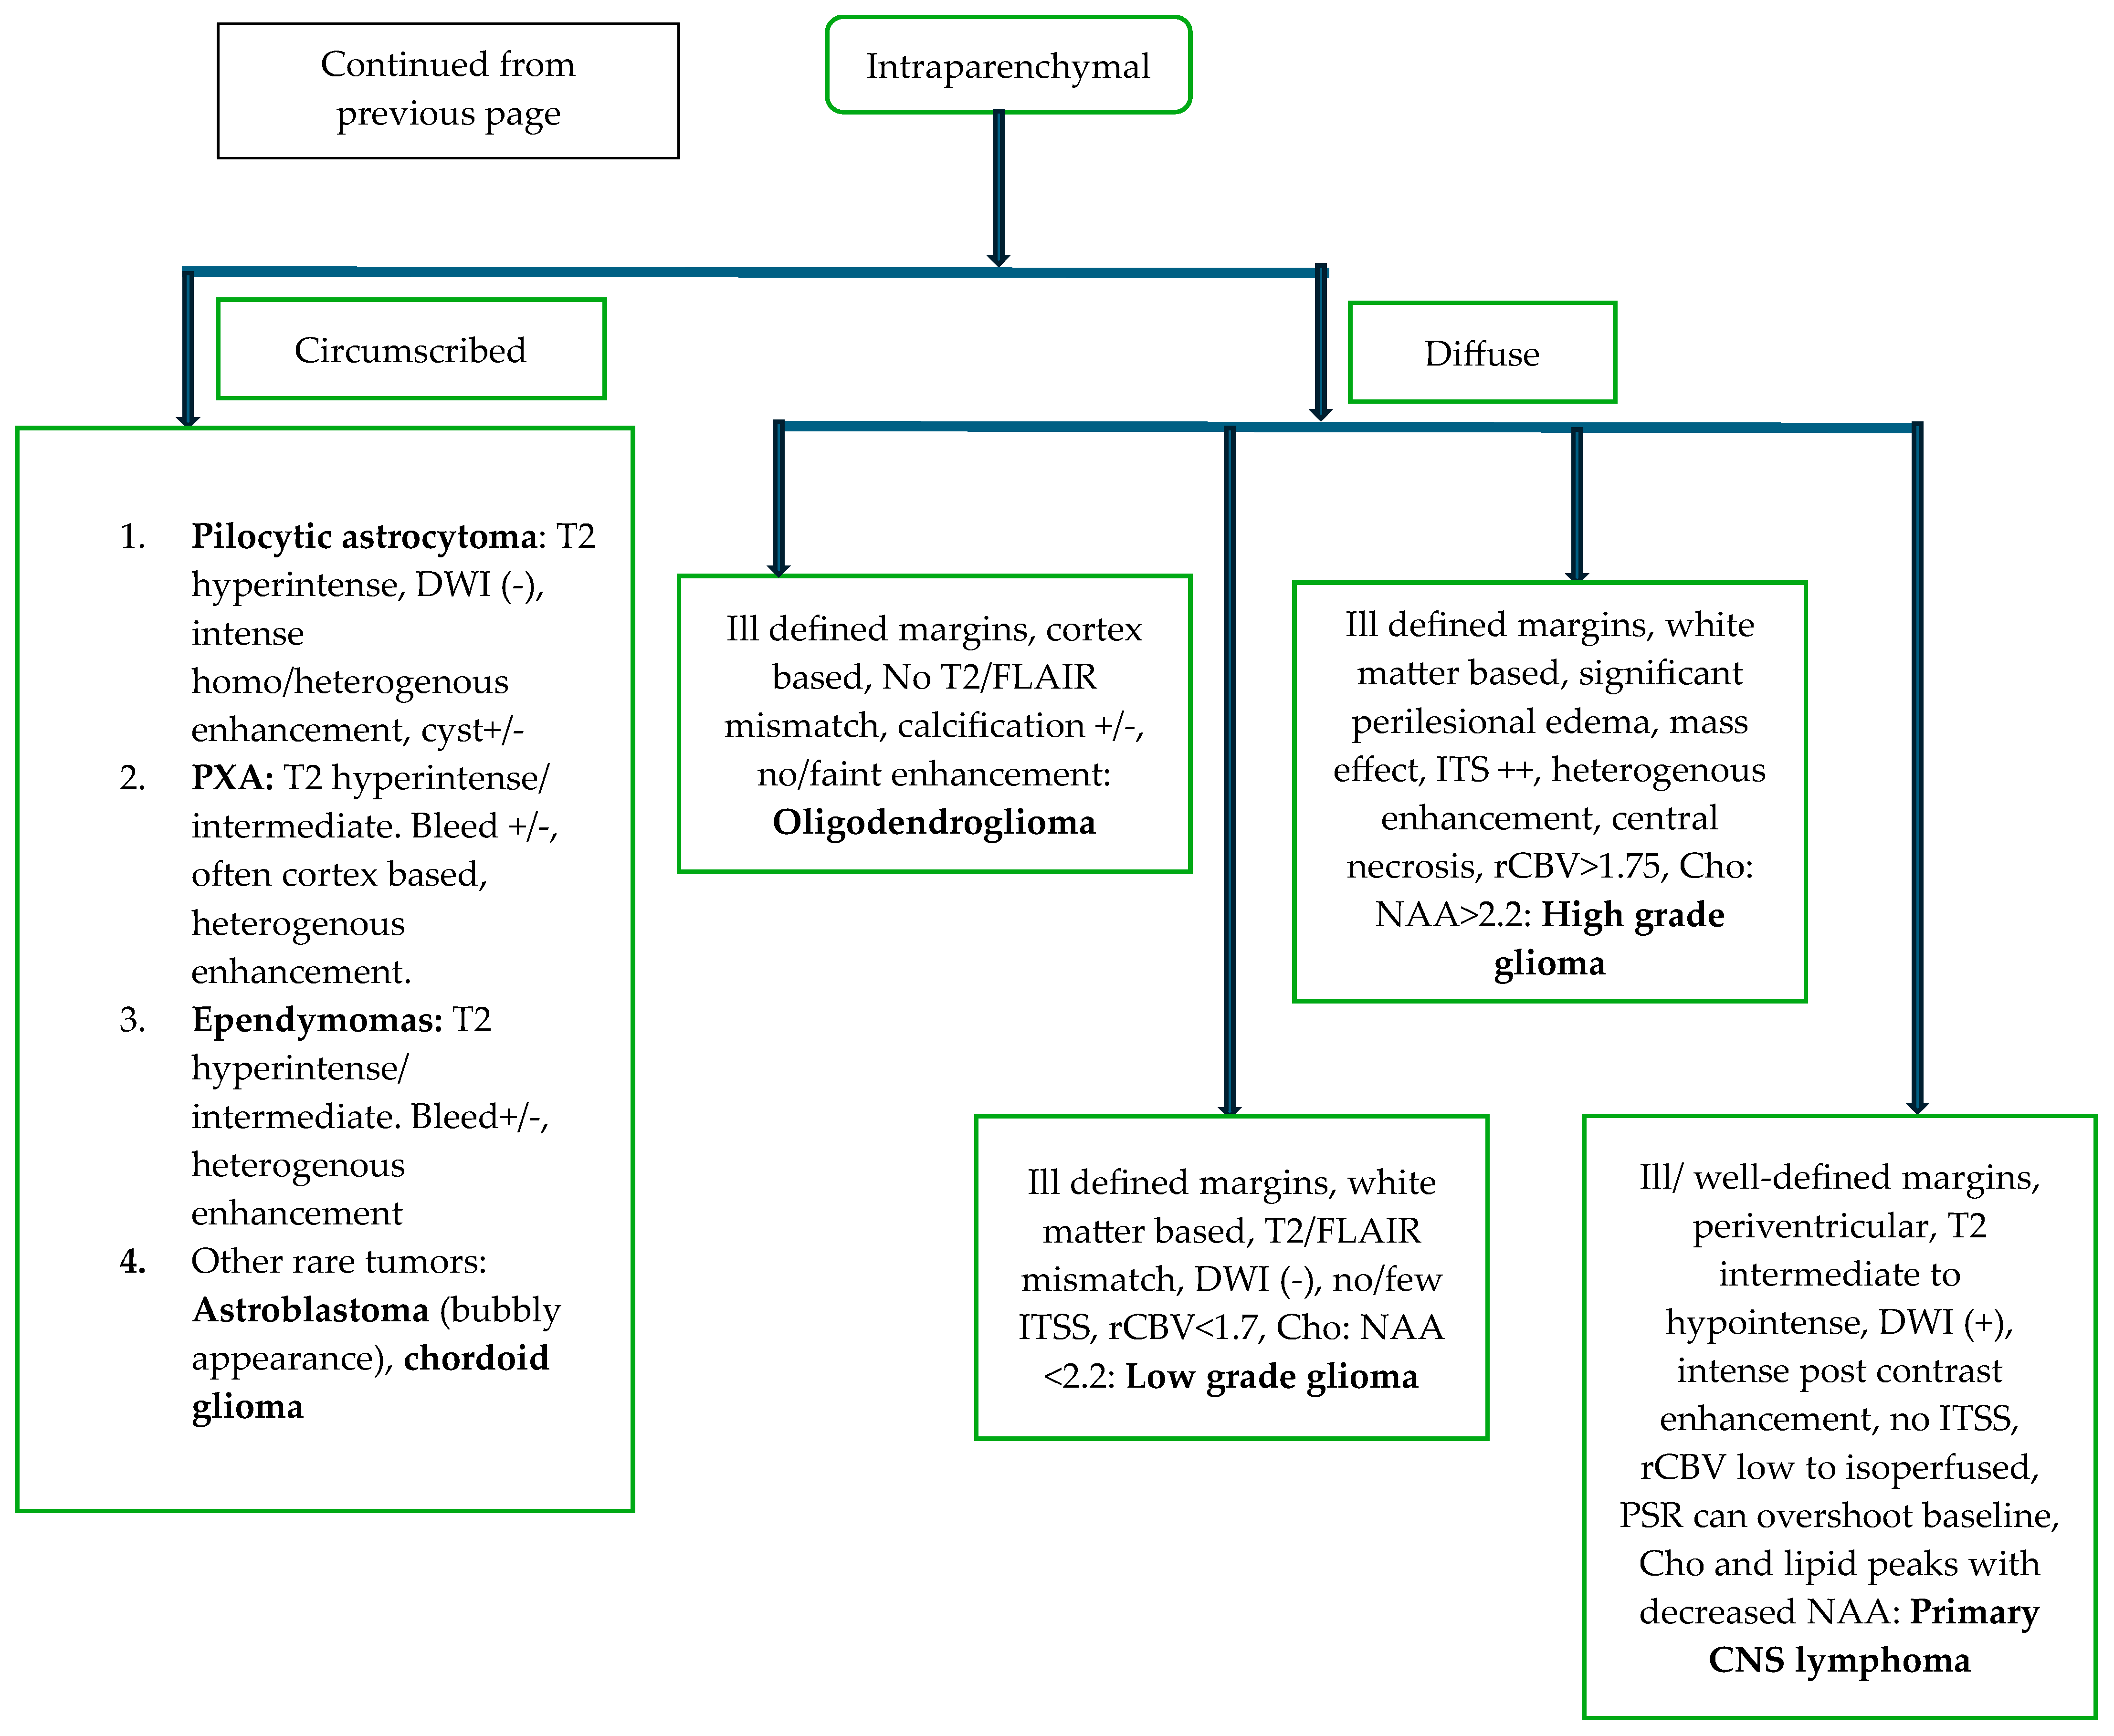

5.2. Diagnosis